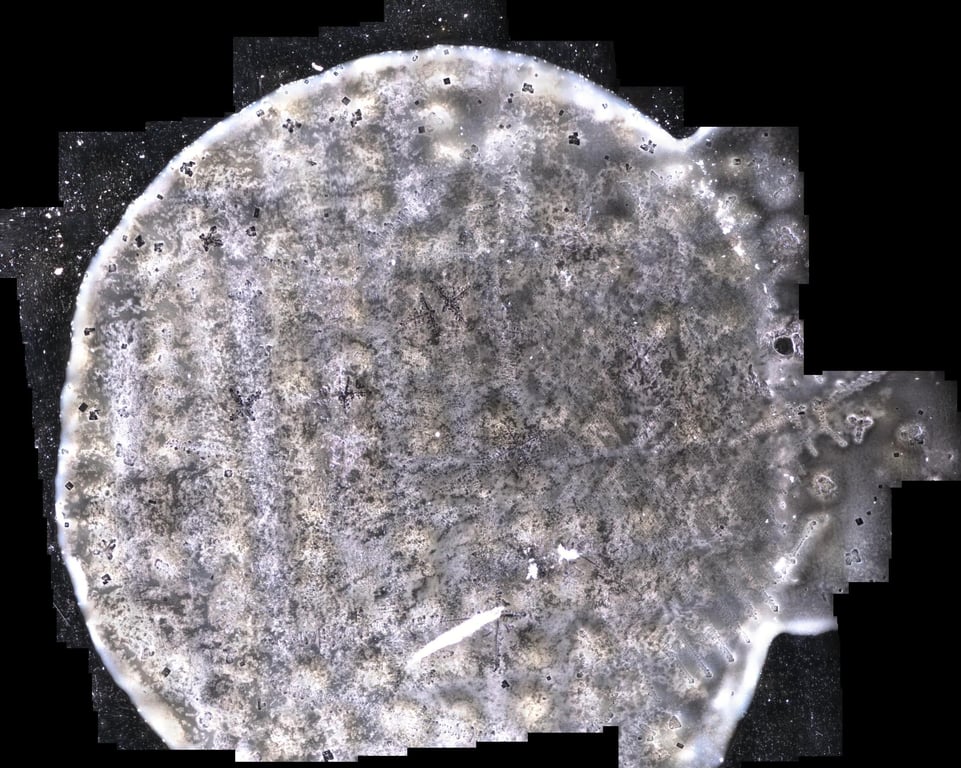

Одно из таких исследований было проведено в Австралии доктором Дэвидом Никсоном, семейным врачом. Доктор Никсон исследовал несколько флаконов вакцин Pfizer из замороженного состояния и до нескольких месяцев сушки на предметном стекле микроскопа.

Его выводы согласуются с другими опубликованными результатами тестирования и изображениями. В целом вещество Pfizer представляет собой тонкий гель, а не прозрачную жидкость.

Под микроскопом из замороженного состояния они выглядят как снежинки или “конфетти”:

В некоторых местах сразу видны более крупные структуры, но многие другие появляются после размораживания. Если оставить их на несколько часов, структуры растут и становятся больше.

Характерные структуры включают квадратные и прямоугольные формы, а также волокна или “ленты”. Они, как правило, вырастают до очень больших размеров по микроскопическим меркам.

Структуры, обычно встречающиеся во флаконах Pfizer: